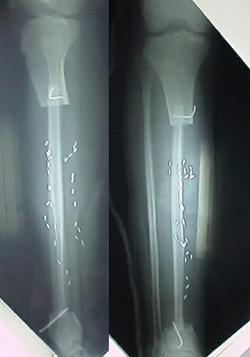

左経骨エナメル上皮腫

(8才で発症、その後24才まで運動は全く×)

No.02

左経骨切断、右足の腓骨(膝と足首の間の細い骨)を移植

(中学三年で手術、その後三年動けず)